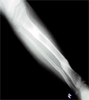

Developed chronic osteoyelitis and treated with wide excision and ilizarov bone transport

Progress

Bone transport with docking after three months

Complete union after five months